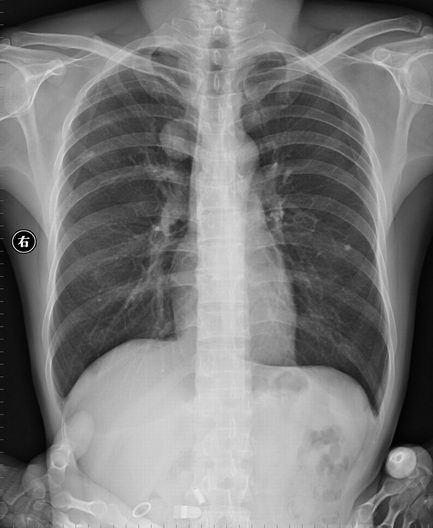

以下是引用sdqzwyx在2006-8-13 8:29:00的发言:[br][br]右上纵隔旁示类圆形密度增高影,边缘光整。[br]可以考虑:[br]1 首先排除体外异物:胸坠、衣服上的印花、口袋内圆形物件等。[br]2 肺内:若为肺内病变,肯定是良性的,肺结核球、囊肿、错构瘤等。[br]3 来源于纵隔、胸膜、或附近骨骼,病变与纵隔呈锐角,周围骨骼联系不太密切(见过一例来源于骨骼的骨软骨瘤重叠肺内),所以可能性不是太大。[br][br][本贴已被 sdqzwyx 于 2006-8-13 12:35:54 修改过]